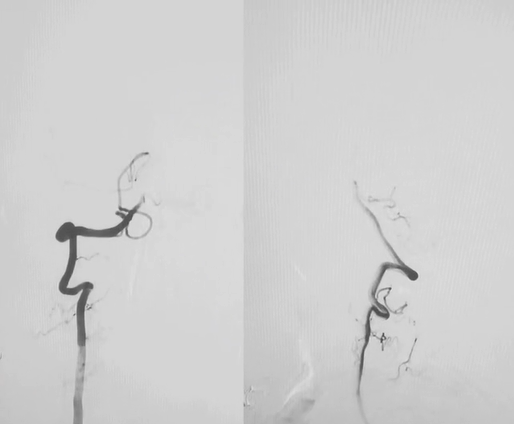

造影定位,锁定病变:

wuwei

左侧锁骨下动脉盗血

锁骨下动脉重度狭窄